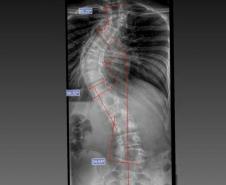

Laura era portadora de escoliose e, em agosto de 2025, realizou a cirurgia de correção da coluna, o que lhe permitirá ter uma vida normal de agora em diante. Moradora de Bom Sucesso do Sul, região Oeste do Paraná, é acostumada a andar a cavalo, mas com o problema na coluna a prática estava longe de ser prazerosa.

O médico João Elias explica que a escoliose é um termo usado para quando você olha a coluna e percebe uma curvatura. Pode acontecer por várias causas, desde uma escoliose congênita, quando o bebê nasce com uma vértebra mal formada e essa vértebra vai levando ao desenvolvimento de uma deformidade na coluna; a neuromuscular, causadas por doenças neurológicas ou musculares, como uma paralisia cerebral, até as idiopáticas, causadas por alterações genéticas e que podem se desenvolver apenas na adolescência.

Segundo ele, o verão é o período em que mais se diagnostica a doença. Por causa do uso de roupas mais leves, é mais fácil notar a alteração na coluna. Caso seja percebida alguma alteração, uma avaliação ortopédica deve ser marcada. “O diagnóstico precoce é importante. Quando a gente percebe que a coluna está iniciando uma curvatura é possível controlar essa curva. Fazer o procedimento com uma curvatura menor permite melhores resultados na cirurgia”, explicou.